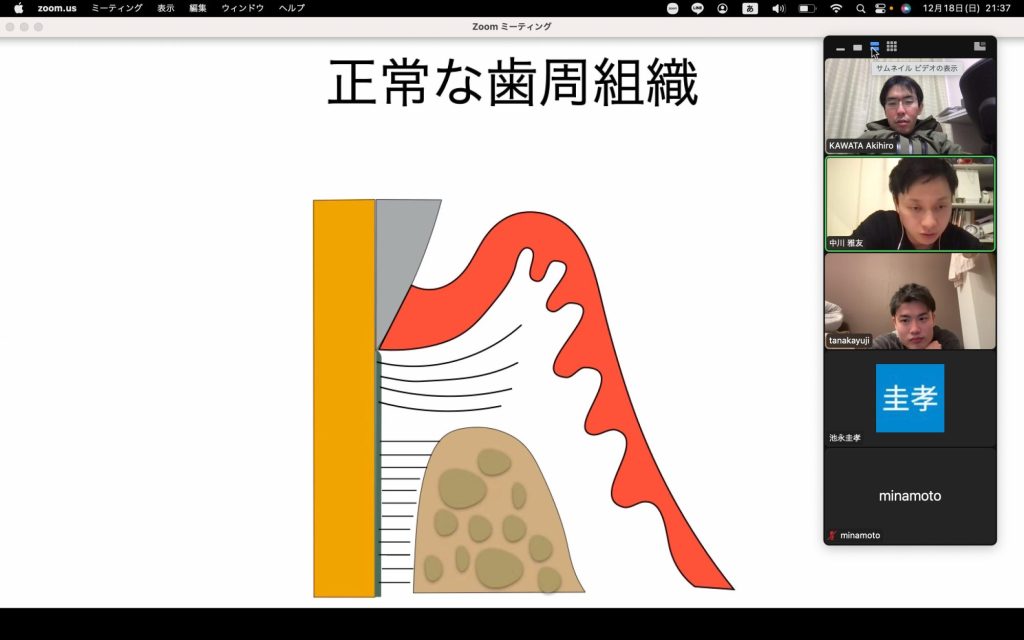

もう一つは歯周病についての内容でした。

もう一つは歯周病についての内容でした。